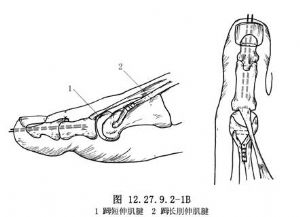

在足背做一個7.5~10.0cm長的弧形正中外側切口,顯露趾總伸肌腱(圖12.27.9.2-2A)。儘量向遠端分離肌腱,並將之切斷。再將其近端通過第3楔狀骨上的隧道穿出,用Bunnell拉出鋼絲縫合法固定在足底的鈕釦上(圖12.27.9.2-2B)。